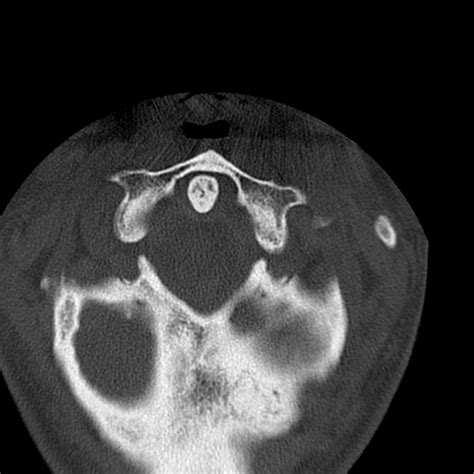

• Computed Tomography (CT) Scan: This is the gold standard for diagnosing occipital condyle fractures. CT scans provide detailed images of the bony structures and can help identify the location and extent of the fracture.

Occipital condyle fractures are classified based on their pattern and mechanism of injury. The most commonly used classification system is the Anderson and Montesano classification, which categorizes these fractures into three types:

Type I Compression fracture of the occipital condyle Axial loading with compression